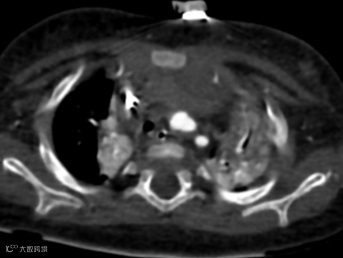

患儿,女,3月龄,出现喘息和喂养困难,肺动脉吊带,右位心。

轴位MIP图像显示心尖指向右侧,异常的左肺动脉(肺动脉吊带)起源于右肺动脉,穿过气管和食管之间,在气管远端分叉处导致管腔轻度狭窄,并压迫右主支气管使其近端狭窄,从而引起上呼吸道症状。